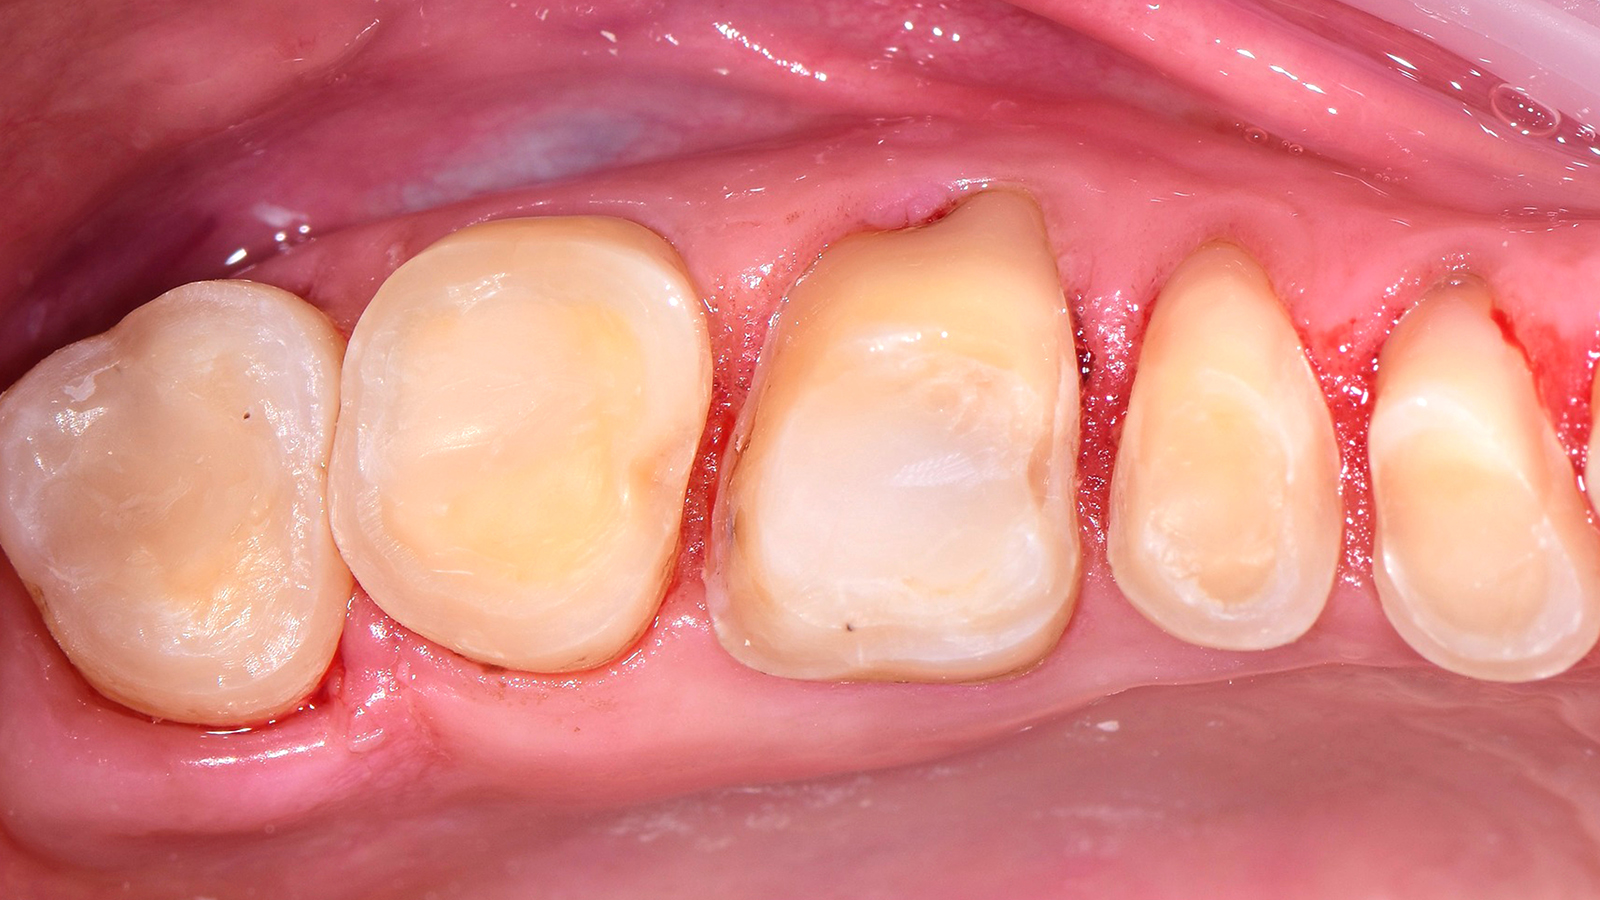

Charisma Bulk Flow ONE is indicated for class III and class V restorations. The Adaptive Light Matching ensures an optimised colour adaptation in ONE shade. Customers have especially made good experience in terms of shade match if the class III restoration has a small labial part or an intact labial wall.

The ONE shade has been optimised to deliver the perfect balance of chroma and translucency that allows the restoration to become virtually invisible. Therefore, the ONE shade can be used with confidence in any Class I and Class II restoration. And this colour adaptation is what we call Adaptive Light Matching.

Using Charisma Bulk Flow ONE without capping layer is beneficial in all clinical cases where a flowable viscosity is ideal during placement, e.g. slot or small cavities or those with tunnel preps, class III restorations with intact labial wall or class V restorations. From a patient perspective, Charisma Bulk Flow ONE is furthermore ideal in cases with little patient compliance or time. By preference or if patients demand a natural morphology, Charisma Bulk Flow ONE can always be used with capping layer, too. Using Charisma Classic, Charisma Diamond or Charisma Topaz on top might be advisable in big cavities or cusp replacements.